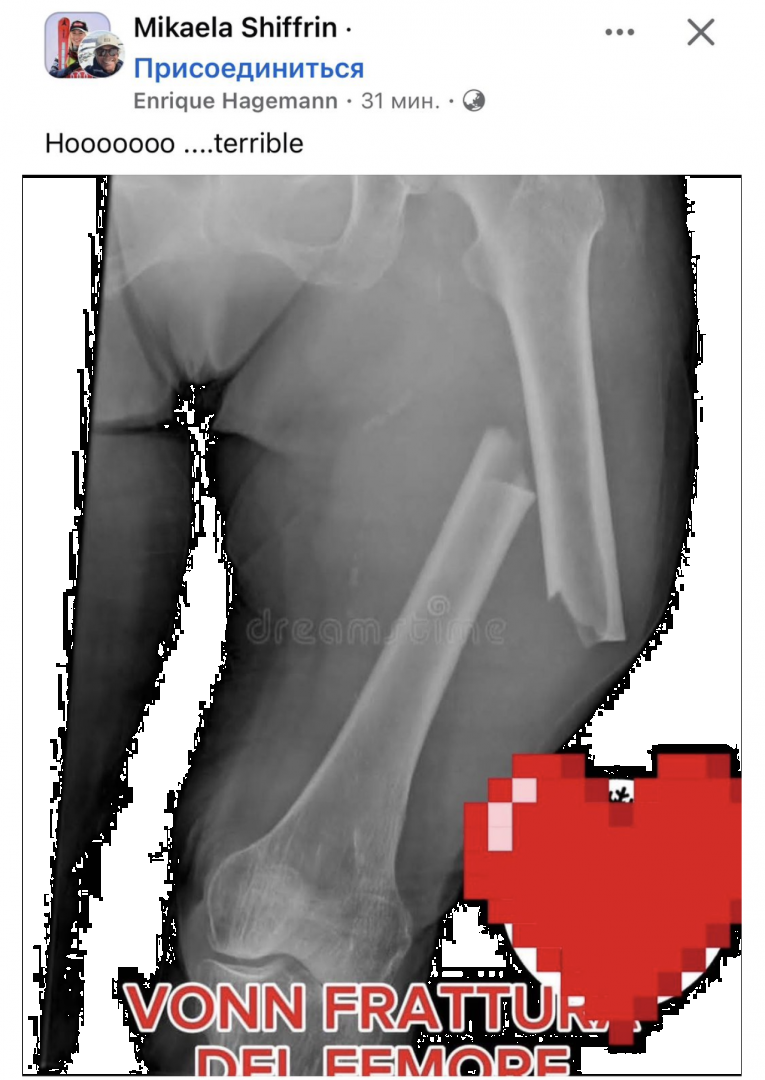

Диагноз - перелом бедра.